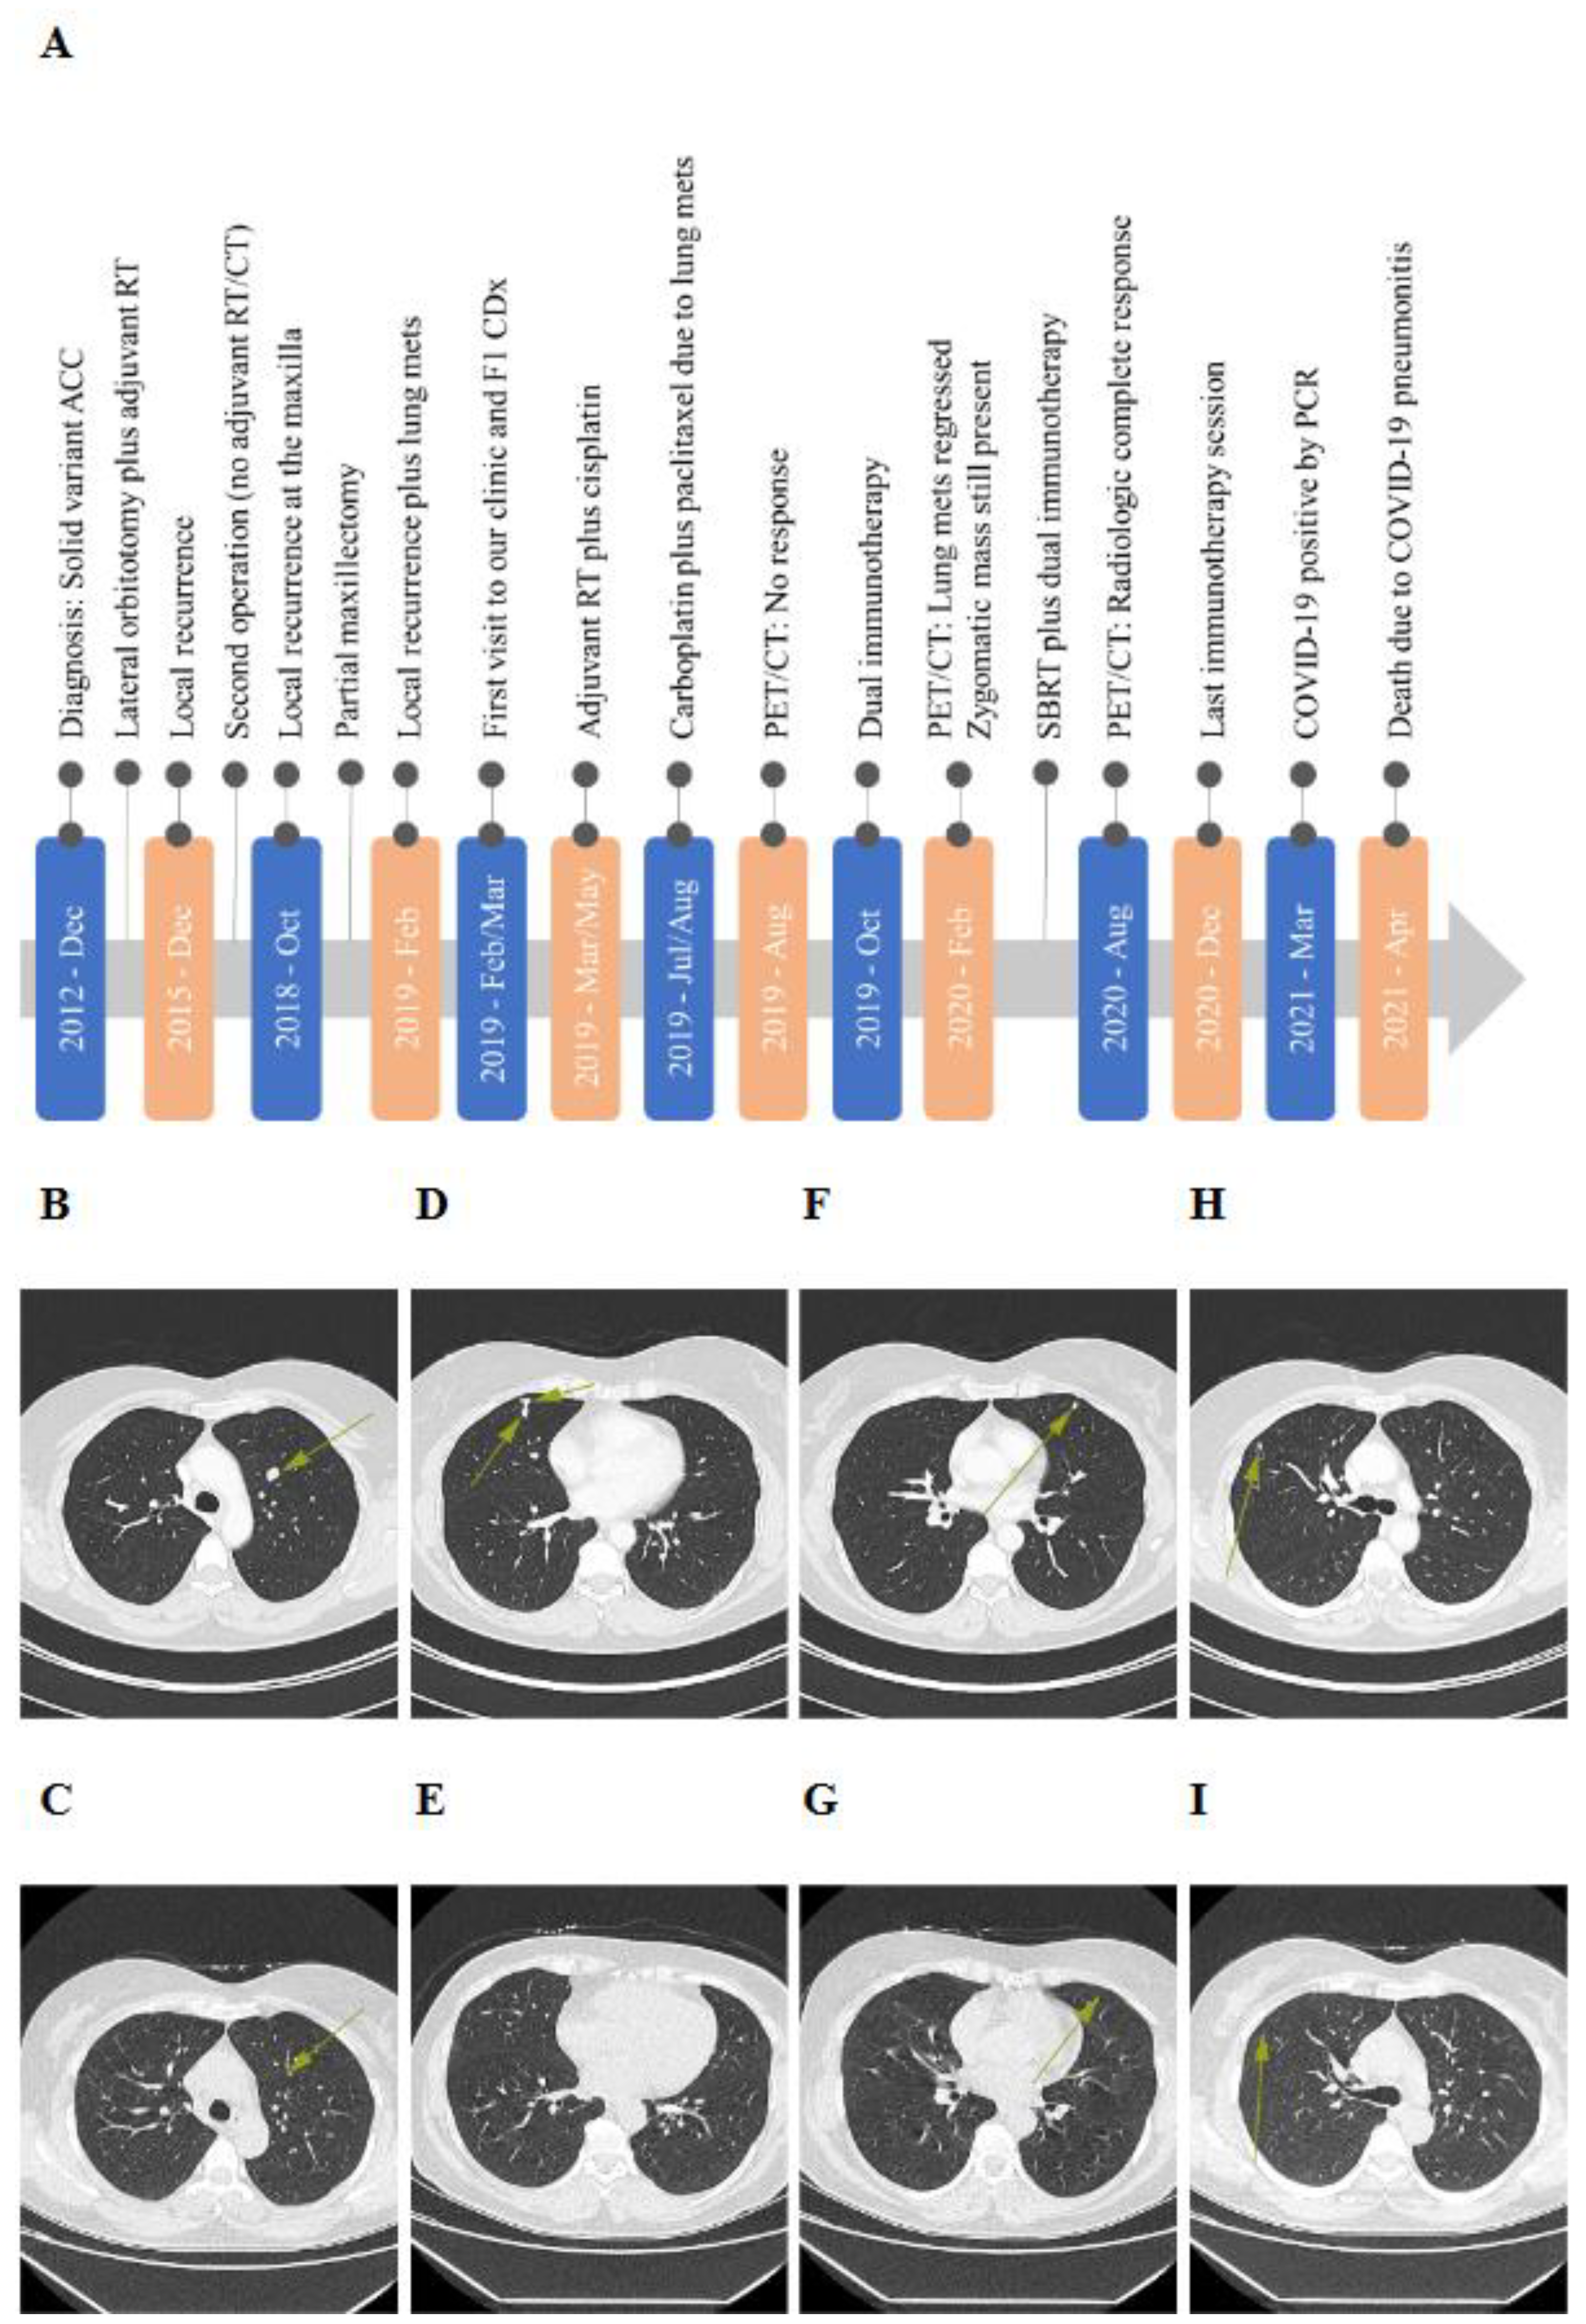

Case Presentation